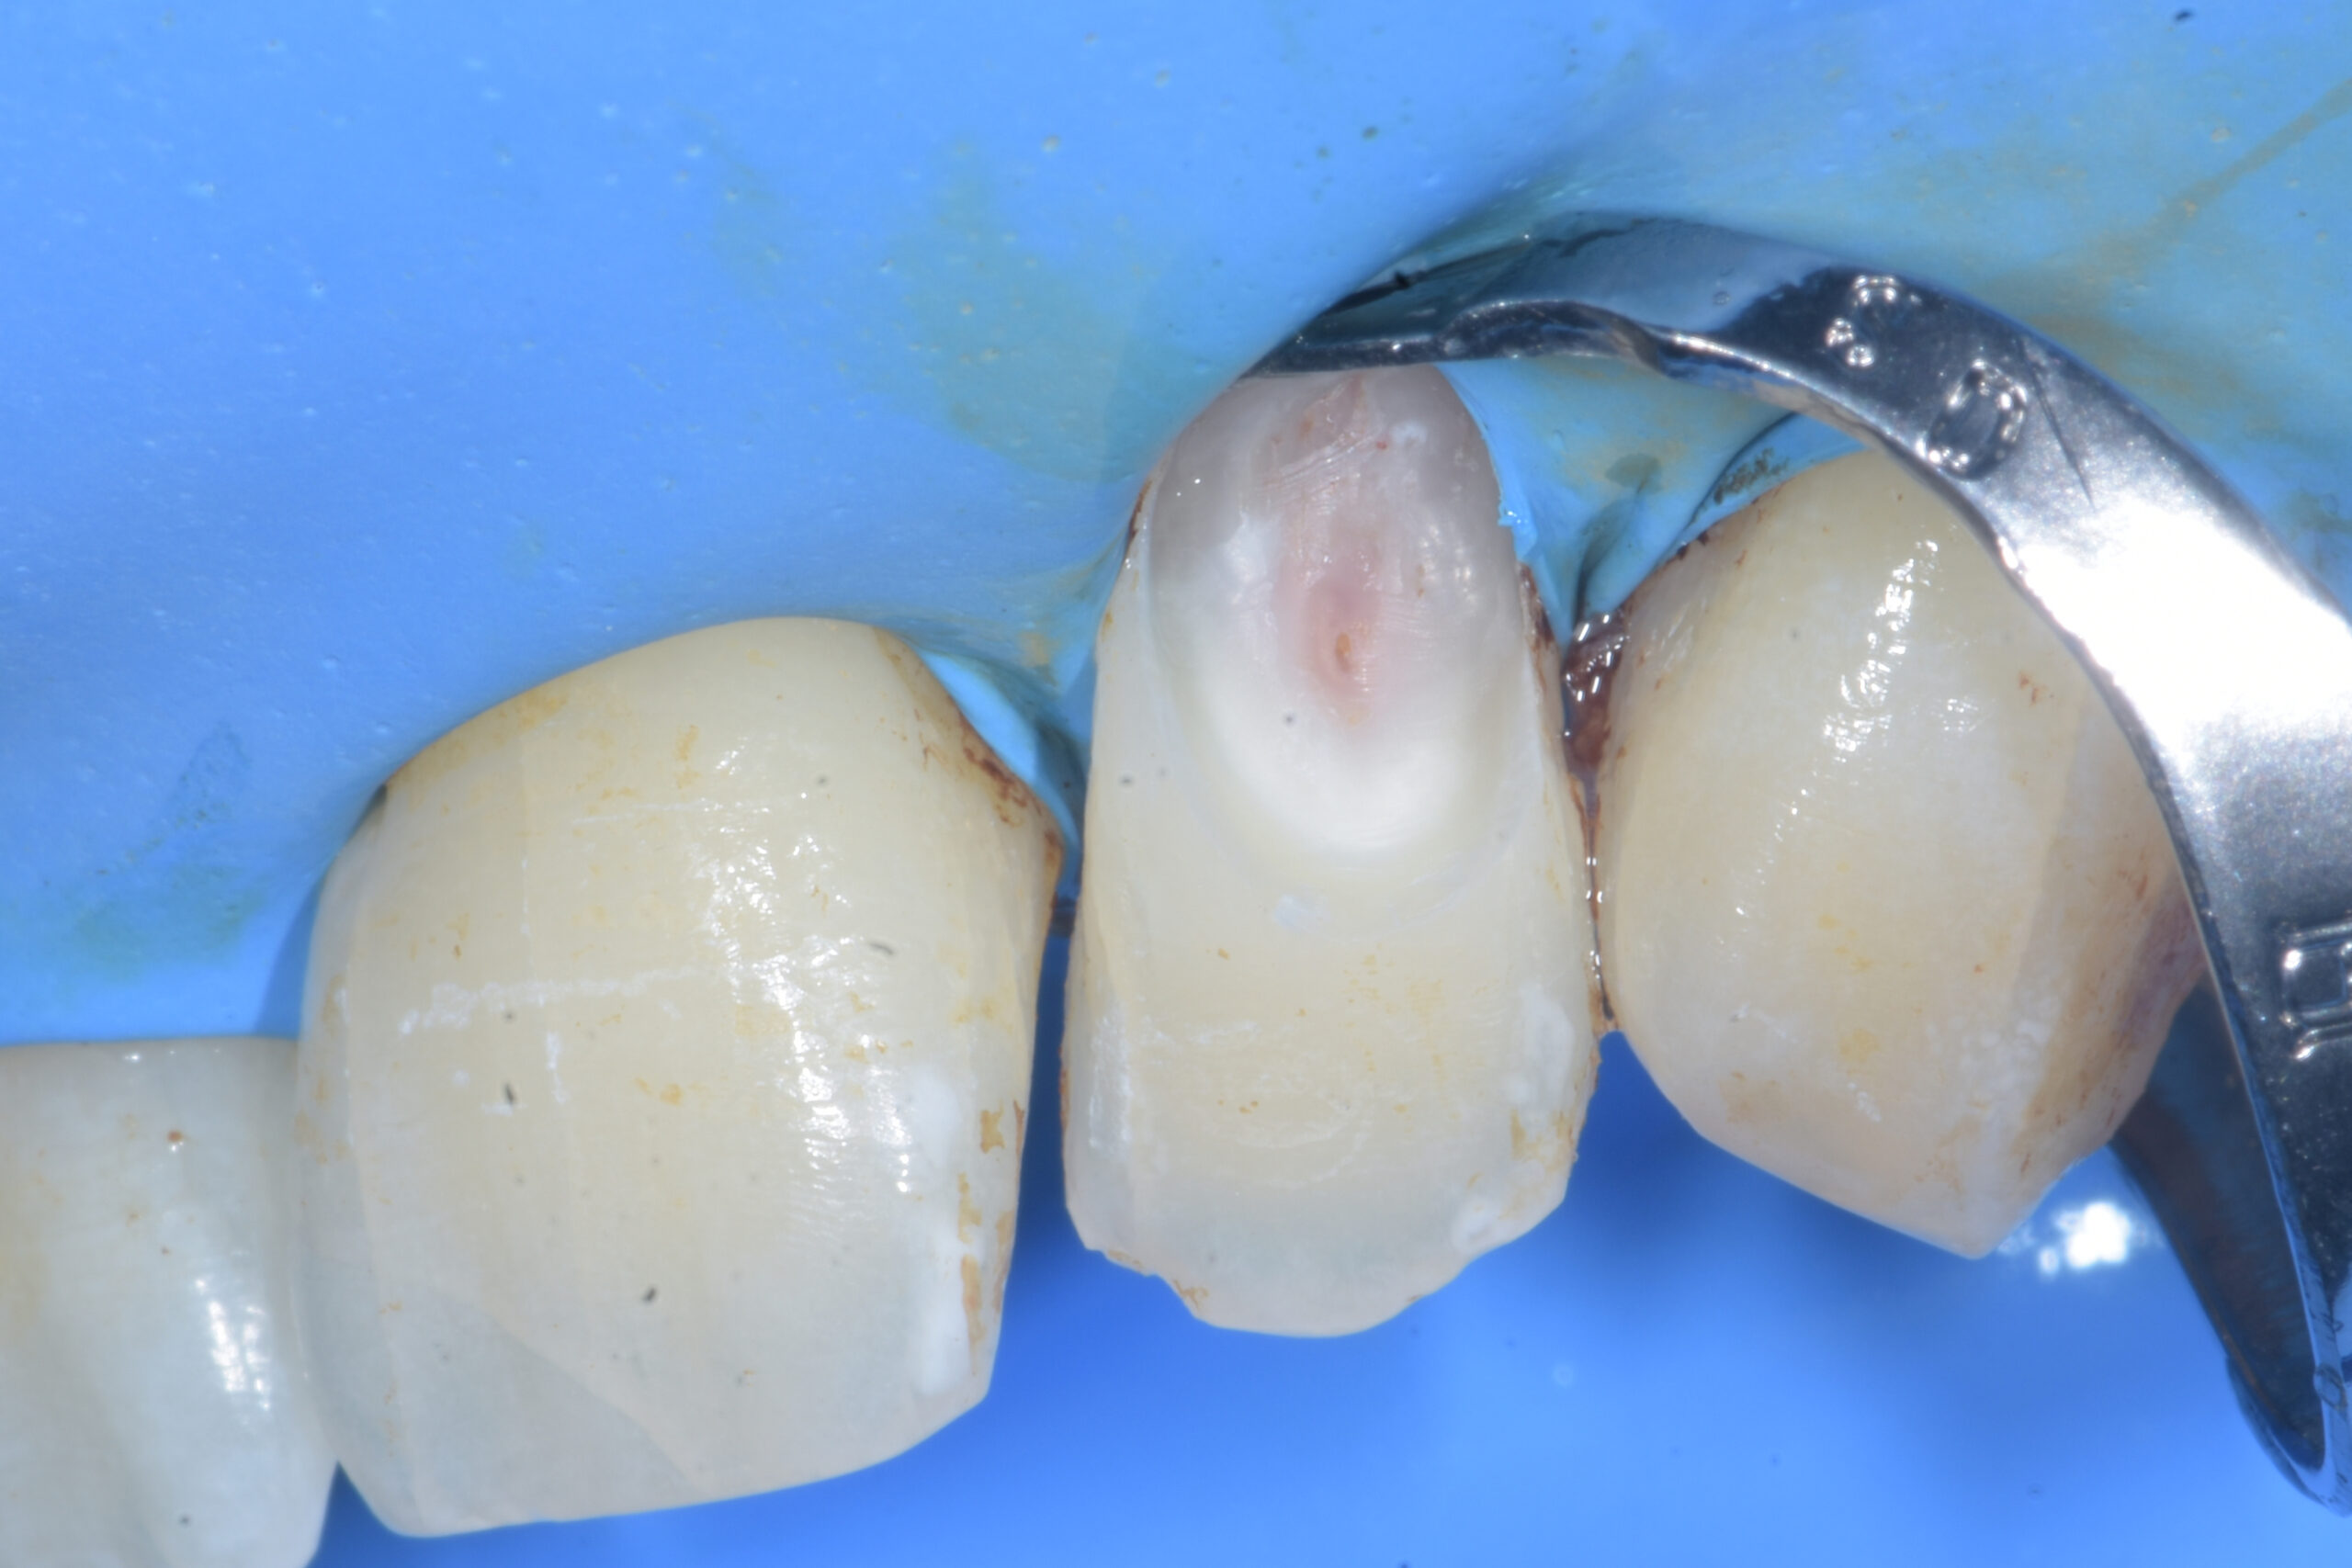

La pulizia della lesione viene eseguita con l’impiego di una pallina diamantata su manipolo rosso e di una rosetta in carburo di tungsteno su manipolo blu (Figura 3).

Al termine di quest’ultima fase, l’elemento viene isolato con diga di gomma mediante la tecnica dell’uncino accessorio (Figura 4).